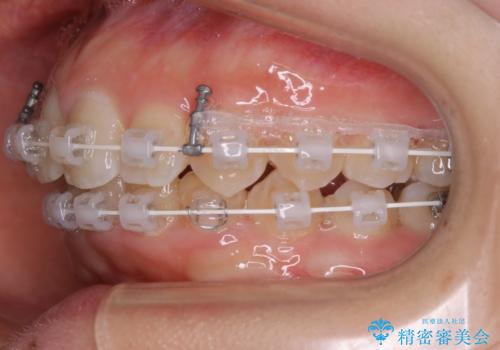

- 矯正装置

- ワイヤー矯正 審美装置

右下の隙間を閉じるため、歯の数を合わせるため、右上の小臼歯を一本抜歯しています。